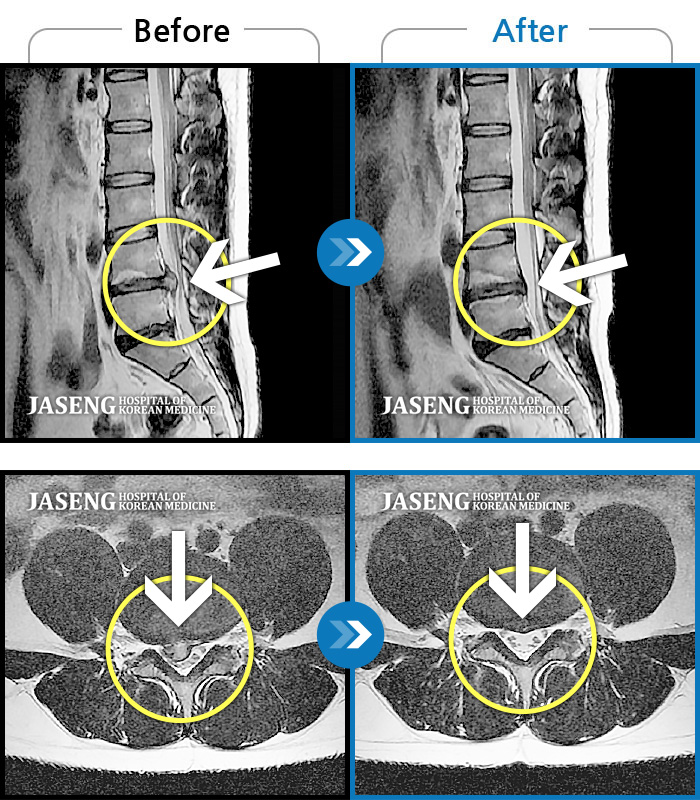

허리디스크

일산 · 김태용 원장

허리 골반통증이 극심했다.

촬영시기

2021.02.06 ~ 0222.01.15

2022.01.17